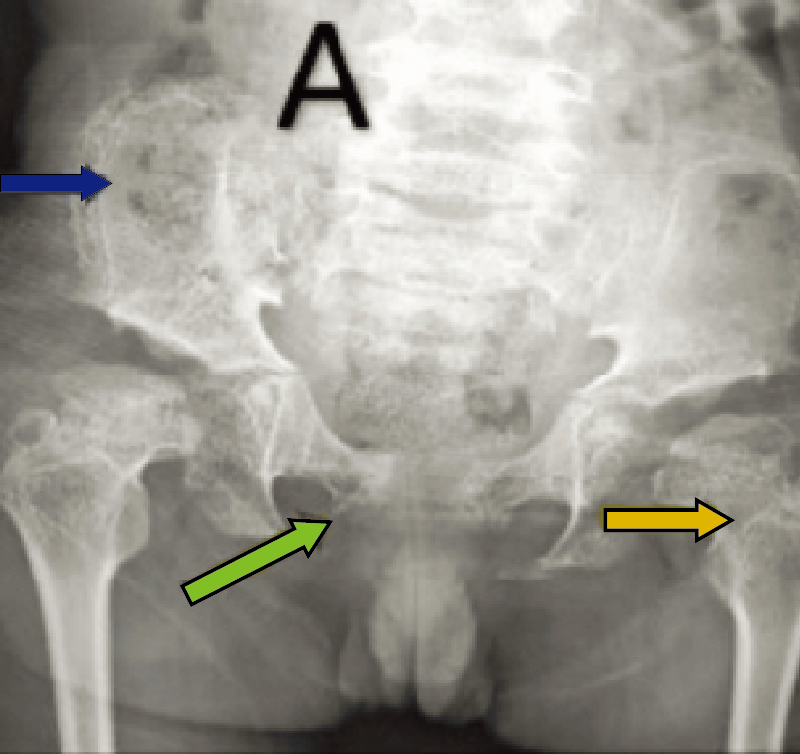

罹患症例の10~20%は両側性。両側性に発症する場合、通常は左右非対称で、異なる病期に発見される(A)。

特徴的な画像所見:初期には関節腔の拡大、大腿骨頭骨端部の骨硬化(B)、前外側の軟骨下骨折線(Crescent sign)を認める。後期は大腿骨頭の扁平化、分節化(A)などがみられる。

A. 両股関節正面像(年齢・性別不明):右は初期、左は進行期のペルテス病。

B. 両股関節正面像(年齢・性別不明):ペルテス病同時期発症例。